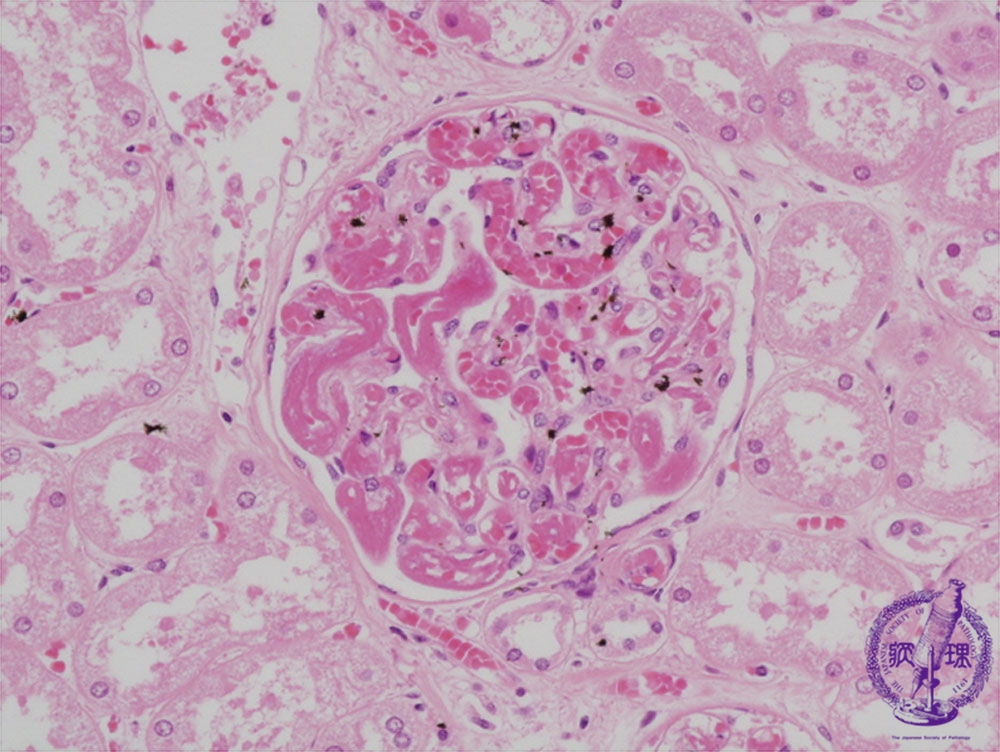

- ★(9)Disseminated intravascular coagulation (DIC)

Microscopic findings ( HE,high power): Fibrin microthrombi within capillaries of glomerular loops (red dotted line).